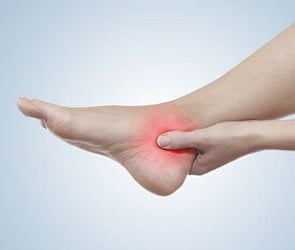

We provide the highest standard of podiatric care, utilising international gold standards of diagnosis and treatment.